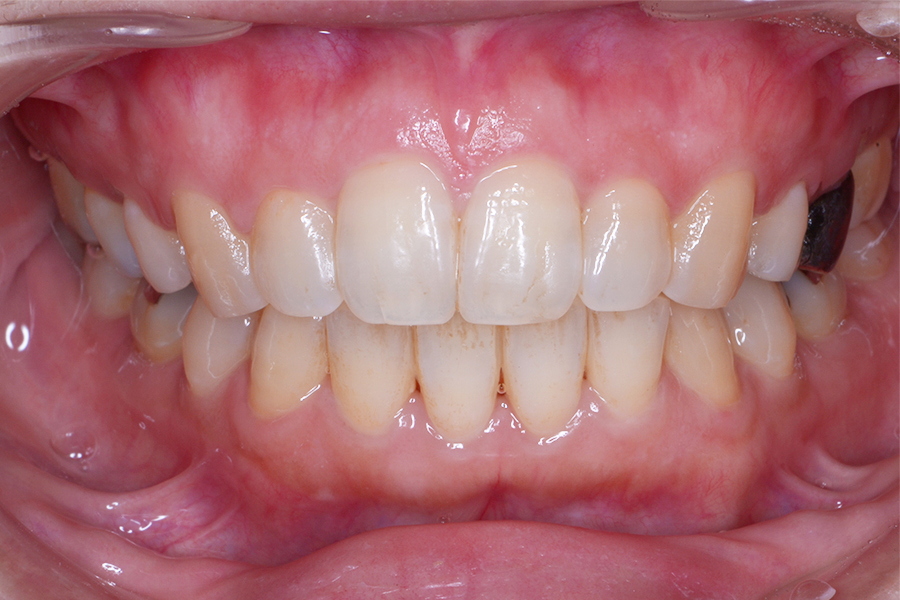

【20代女性】すきっ歯(隙間)と

咬み合わせを良くしたい

【矯正歯科治療】

- 担当医

- 三留先生

- 主訴

- すきっ歯(隙間)と咬み合わせを良くしたい

- 期間

- 治療期間10か月

- 費用

- 治療費35万+20万(別途調整料)

- 治療内容

- ハーフリンガル矯正(上顎裏側・下顎表側矯正)

- 治療に伴うリスク

- 後戻り